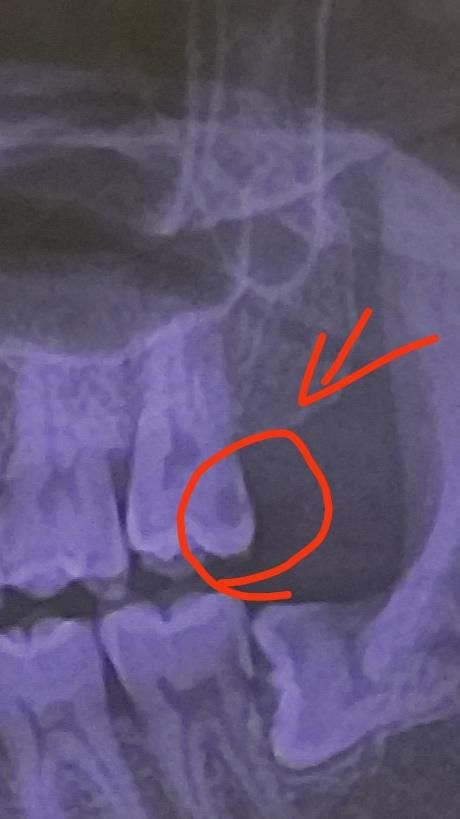

치아 엑스레이 사진에서 동그라미 친부분 충치인가요?

사진은 위 왼쪽 끝 어금니 치과두곳 엑스레이 사진인데요 동그라미친부분에 약간 검은 부분이 있는데 통증은 아직 없고 잘닥고는 있는데 이거 치료받아야할 충치인가요? 아님 그냥 내비둬도되나요?

• 2번 째 사진

일반적으로 엑스레이 상으로 저렇게 보이는건 충치일 가능성이 높습니다. 치료를 하셔야될것같습니다.

치료를 받아야 하는 정도의 심한 충치입니다. 통증이 없다고 해도 충치의 범위가 아주 큽니다.

네 충치로 보입니다만 더 자세히 보기 위해서는 치근단사진을 찍어봐야 합니다 꽤 깊은 충치라 신경치료 가능성도 있어보입니다

사진으로만 봤을 경우에는 해당 부위에 음영이 보입니다 치아 내부에 음영이 보인다는 것은 그만큼 밀도가 낮아져 있다는 것이며 충치가 있을 가능성이 높습니다 치아의 충치가 있다면 치료를 해 준다는 것이 좋습니다.

자세한 확인을 위해서 치과에서 진료를 받아 보는것을 권유드립니다.